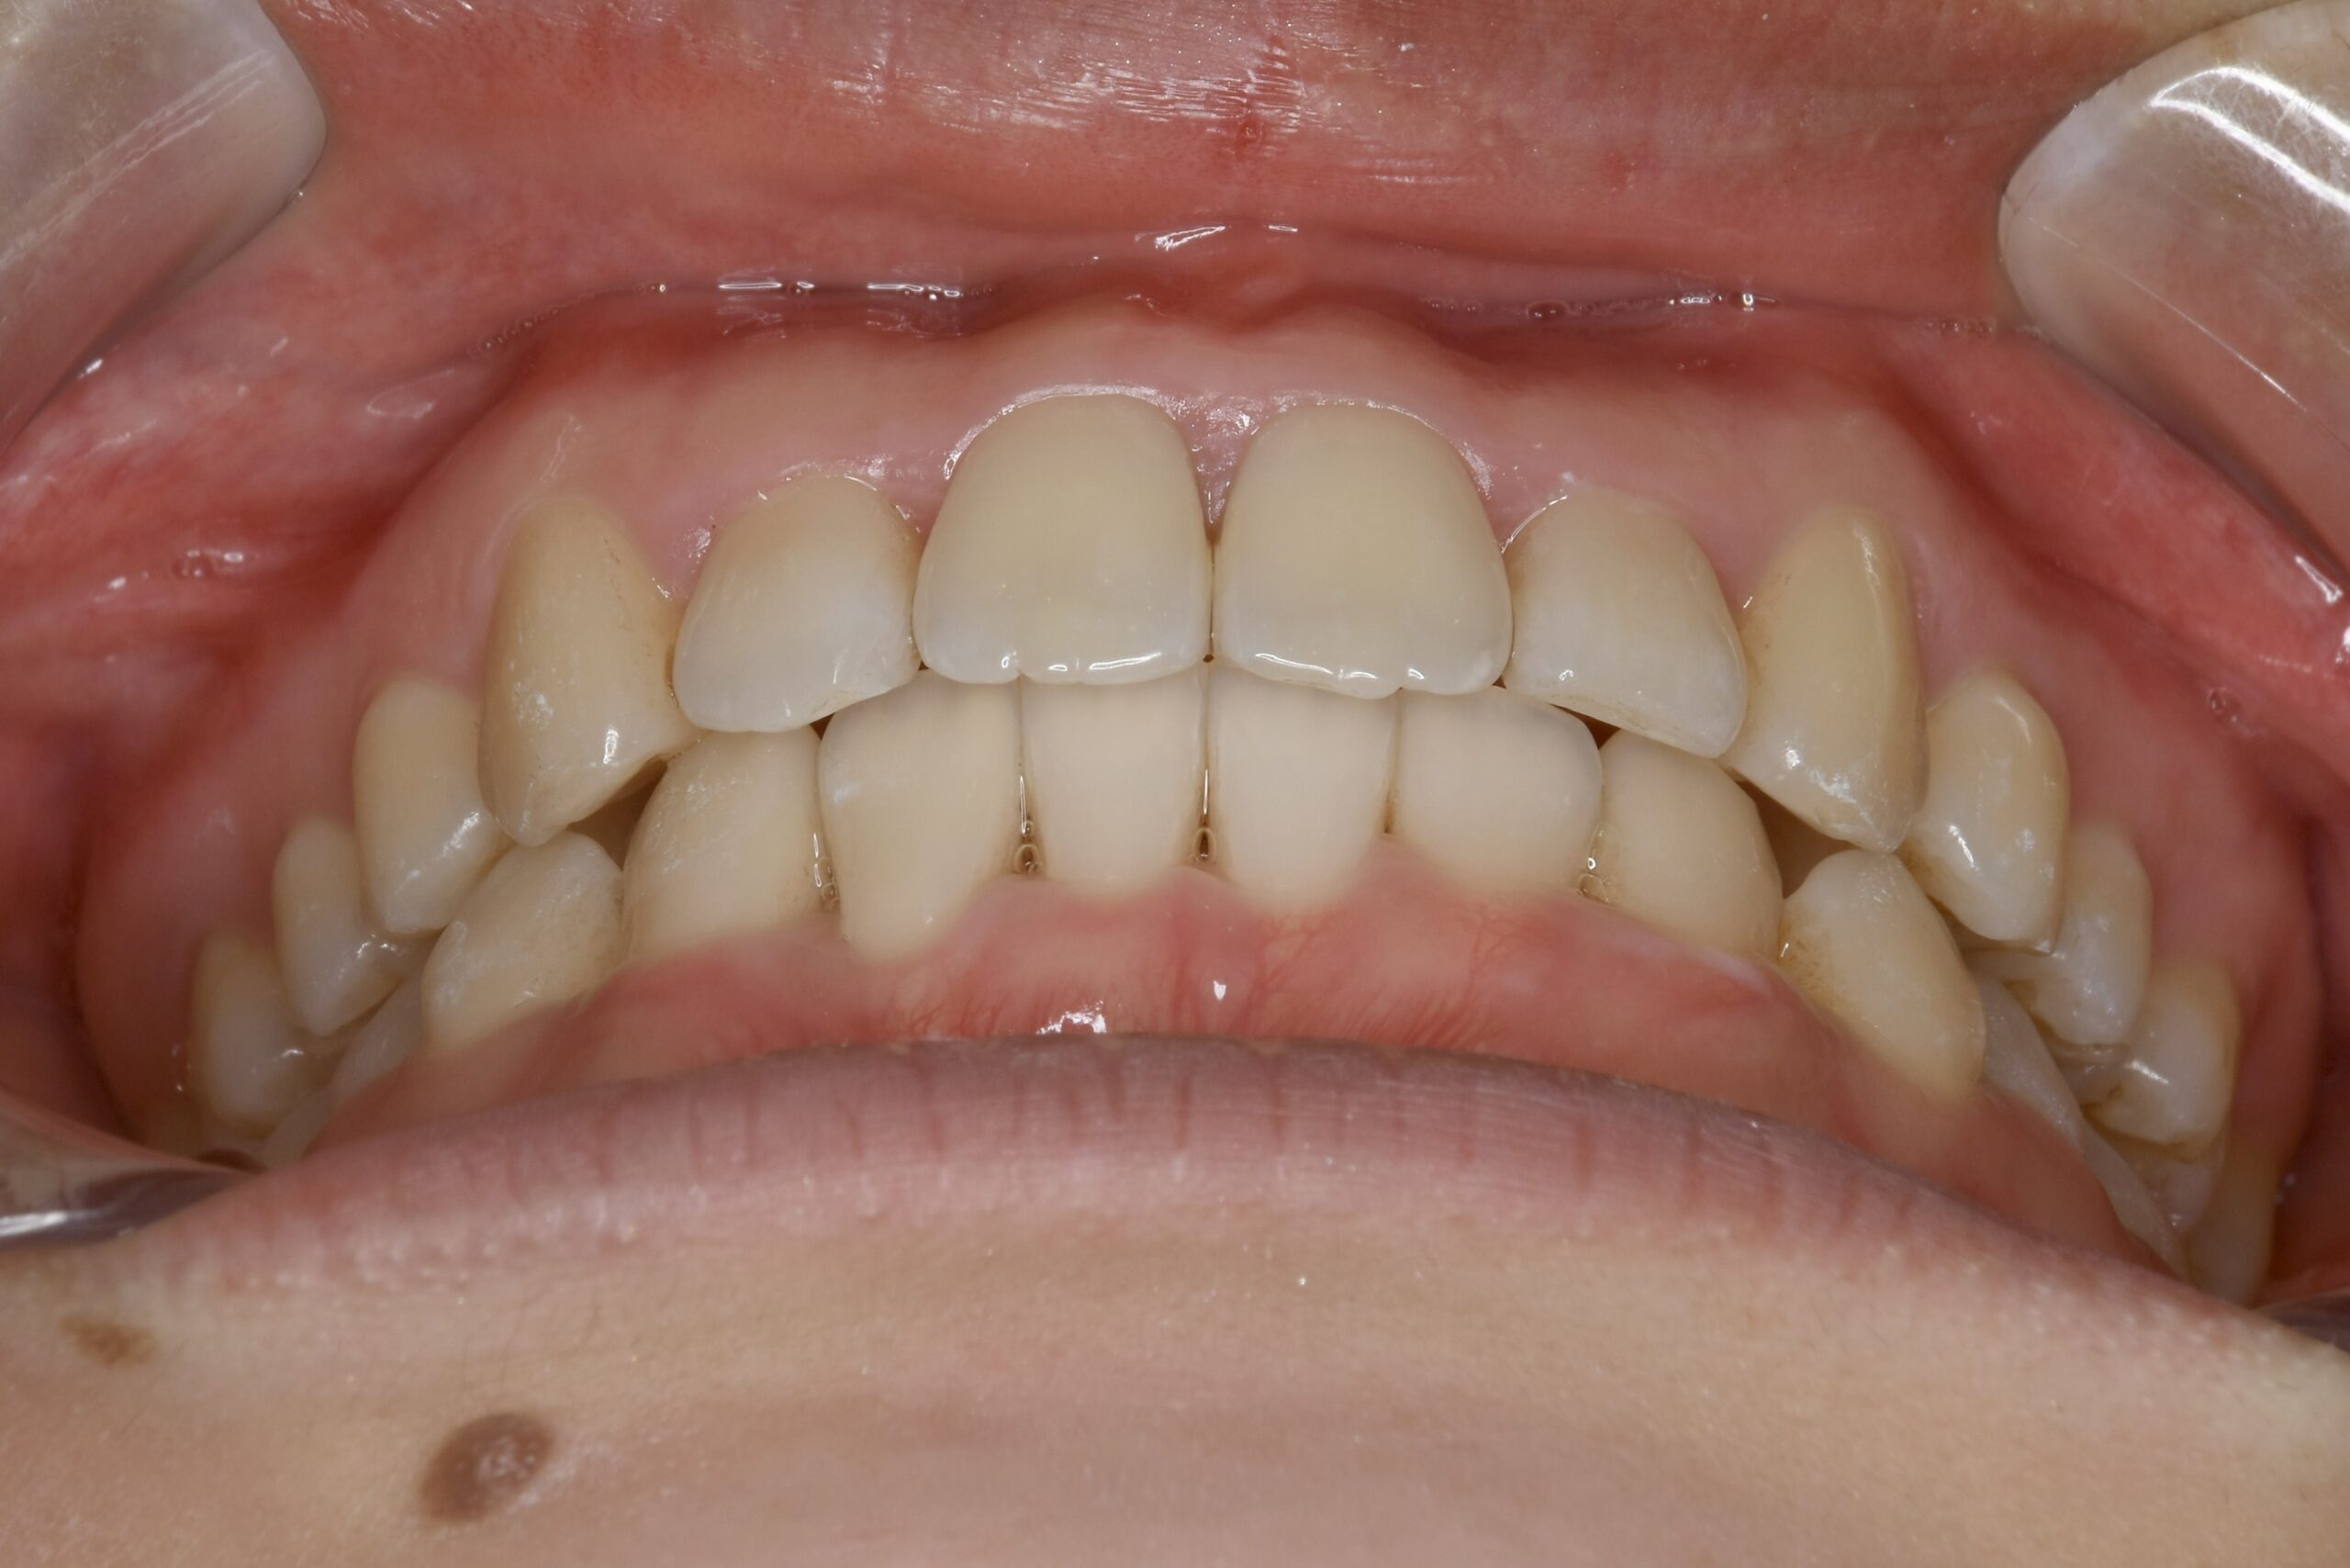

21歳 女性 治療期間:1年1ヶ月

叢生(ガタガタ)

マウスピース矯正装置(インビザライン)

BEFORE

AFTER

主訴

周りの人の歯並びが綺麗で自分の歯並びを治したくなってきた。

診断名・主な症状

叢生

治療内容

上下とも歯並びの横幅を広げながら、でこぼこを解消しました。

マウスピース矯正(インビザライン)

抜歯あり(智歯抜歯)

治療期間

1年1ヶ月

通院回数

10回

費用

85万円程度(税別)

リスク・副作用

痛み、歯肉退縮、歯根吸収、抜歯に伴う出血や腫れが生じることがあります。